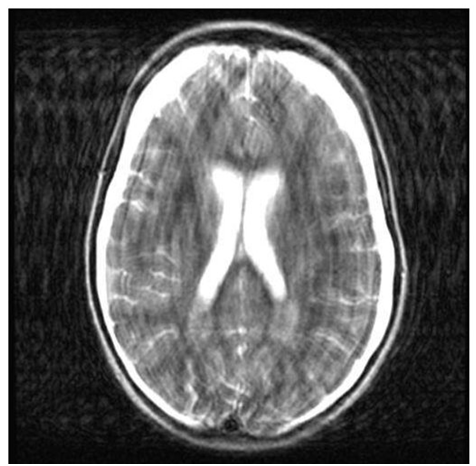

Одним из важных параметров МРТ-изображений является Echo train length (ETL), который, по сути, определяет количество строк К-пространства, заполняемых за одно время повторения TR.

Для ИП типа простого SE (спин-эхо) ETL равен 1, т.к. заполняется одна строка. Для быстрого спин-эха (FSE – Fast SE) с такими же TR и TE этот параметр больше 1 – заполняется по несколько строк сразу. Для UltraFSE и других сверхбыстрых последовательностей – все строки за один TR. Чем выше ETL, тем меньше в итоге времени требуется на получение изображения, но при этом контраст снижается, а шум возрастает. Разумное значение ETL выбирается оператором с учетом задачи и исследуемого органа. Например, для подвижных органов (сердце, легкие, кишечник и т.п.) использование ИП с высоким ETL позволяет снизить влияние движений на резкость слайсов.

Из-за явного влияния на контраст и шум изображений этот параметр полезен как при выборе оптимальных серий, так и при анализе ошибок и устранении выбросов из датасета.